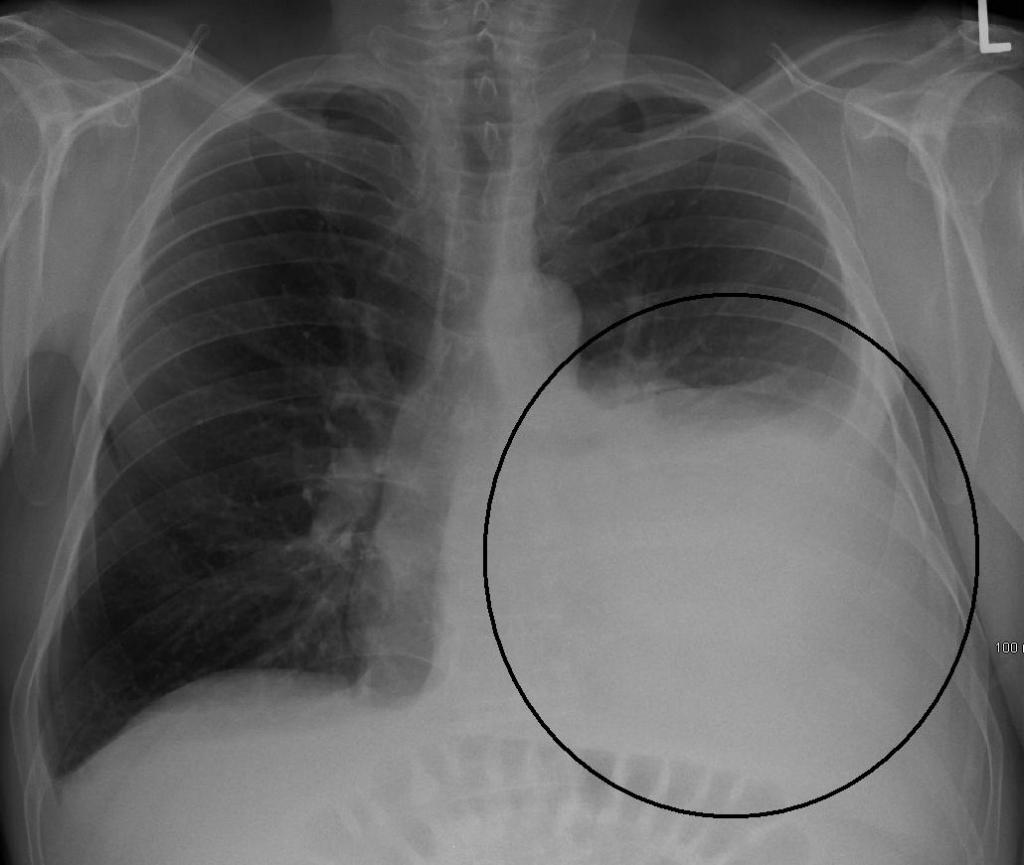

- two or more lobes are affected on an x-ray;

- Severe degree. The patient has symptoms of intoxication: body temperature is above 38 degrees. Respiratory failure is observed, hemodynamics are disturbed. With complications, septic shock can be diagnosed. In KLA, leukopenia or leukocytosis. Infiltration is bilateral, with a rapid increase in the affected area.

Usually the disease begins acutely, a cough appears with mucopurulent sputum. During the examination, shortening of percussion sound, weakening of bronchial breathing, moist small-bubbling rales, crepitus are noted. In blood tests, leukocytosis is observed. X-rays show zones of infiltration.